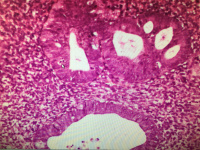

子宫内膜诊刮

性别

女

年龄

40

临床诊断

宫血

一般病史

不规则阴道流血半月

标本名称

宫内膜

大体所见

灰红灰白碎块组织

请问各位老师,这类宫内膜是否怎么诊断?简单型增生,局灶复杂型增生是否够的上,谢谢?

局灶复杂型增生

是不是有非典型增生

图5看着像非典型增生。